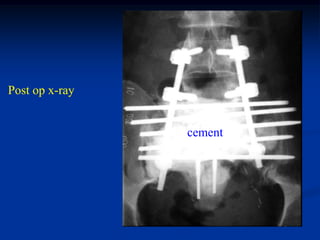

Wide resection entire                   CD rod

sacrum and recon with           L-5

CD rods and Steinman

pins prior to cementation

Steinman pins

CD rods

After cementation

cement sacrum

Post op x-ray

cement

L-4

L-5

Lateral view

cement coccyx